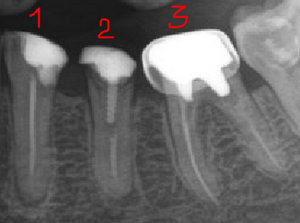

Если при просмотре рентген-снимка пломбировка канала смотрится как нормальная, изменений на верхушке корня нет, то перепломбировывать не надо. Любое вмешательство увеличивает риски, проще говоря, можно сделать хуже.

Другая ситуация, если на снимке выявлены пустоты, не до конца запломбированные каналы, есть разрежения, изменения на верхушке корня, либо зуб ранее побаливал при надавливании, накусывании, слегда поднывал, например при изменении погоды и т.д. В таких случаях лучше зуб перелечить, чтобы избежать проблем с будущей коронкой.